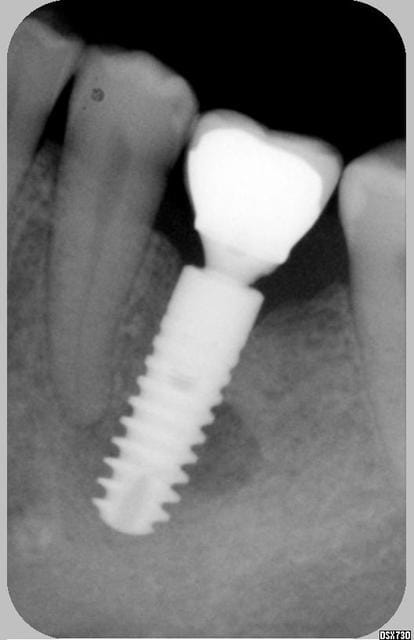

Je revois la patiente aujourd'hui et voila la radio: l'image suspecte a disparu presque complètement, implant complètement silencieux et fixe... todo isso e muito bem!!!

oui Chicot mais s'agit il de fibres ou d'os moins dense ? les limites ne sont plus nettes comme au début.